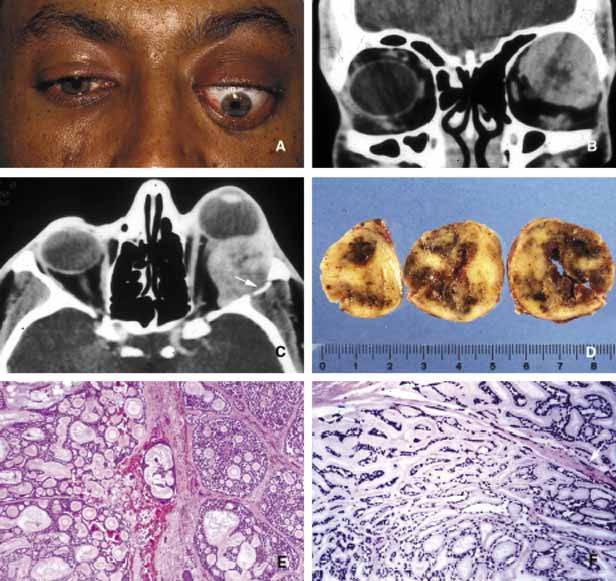

Primary epithelial neoplasms of the orbit originate from the ductal and acinar epithelium of the lacrimal gland.167,168 The most commonly encountered lacrimal gland tumor is pleomorphic adenoma (benign mixed tumor) (BMT). This neoplasm is known as a “mixed” tumor because it is composed of a mixture of epithelial and stromal elements (Fig. 14). The epithelial elements of the tumor consist of glandular and ductal formations that may develop squamous metaplasia and small keratin filled cysts. The stroma is composed of myxoid tissue that may contain cartilage and bone. In most cases the BMT of the lacrimal gland is multilobulated and surrounded by a fibrous capsule. If additional smaller lobules are present in the vicinity of the main lesion, these satellite nodules are individually encapsulated as well. When malignancy develops within a BMT it is classified according to its predominant histopathologic component as adenocarcinoma within pleomorphic adenoma, adenoid cystic carcinoma, or poorly differentiated carcinoma. Malignant transformation may happen as a rapid growth within an unknown tumor or may take place decades after diagnosis of the BMT.169 Adenoid cystic carcinoma, the most common malignant tumor of the lacrimal gland may also develop de novo. This is a highly malignant neoplasm that can be seen in adolescents and may develop rapid extension into the adjacent structures including the cranium by direct invasion and to the base of the skull by painful perineural invasion.170,171 The histopathologic appearance of adenoid cystic carcinoma may present as several variants including the most common “Swiss cheese” pattern that consists of cribriform clustering of small basophilic tumor cells surounded by thick basement membrane (Fig. 15). Other types including diffuse basaloid, sclerosing, tubular, and comedocarcinoma are known to exist.172

Fig. 14 Benign mixed tumor (BMT). Coronal CT (A) depicts a well-delineated mass in the superior lateral orbit causing inferior medial dislocation of the globe. Frame B shows multilobulated nature of pleomorphic ademona (benign mixed tumor). The tumor nodules are bisected to show the encapsulation and the focal nature of the tumor masses; the nodule on the right was discovered inferior to the main lesion as a satellite mass (B). Histopathologically pleomorphic adenoma is composed of a mixture of glandular (g) and myxoid (m) tissues (C, D). Some of the glandular formations may develop squamous metaplasia and distend to form cystic space (c) secondary to keratin accumulation. (D)

Fig. 15 Adenoid cystic carcinoma. A large superior temporal mass causing marked proptosis of the eye and inferior displacement (A, B, C). The axial CT scan depicts the infiltration of the lateral wall with the tumor (arrow) (C). Serial sectioning of the tumor showing focal areas of hemorrhagic necrosis and cystic changes (D). Frames E and F depict the histopathological appearance of adenoid cystic carcinoma forming a “Swiss cheese” pattern with proliferation of atypical, irregular, glandular structures. Peripheral nerve sheath involvement (arrow) is seen in frame F.